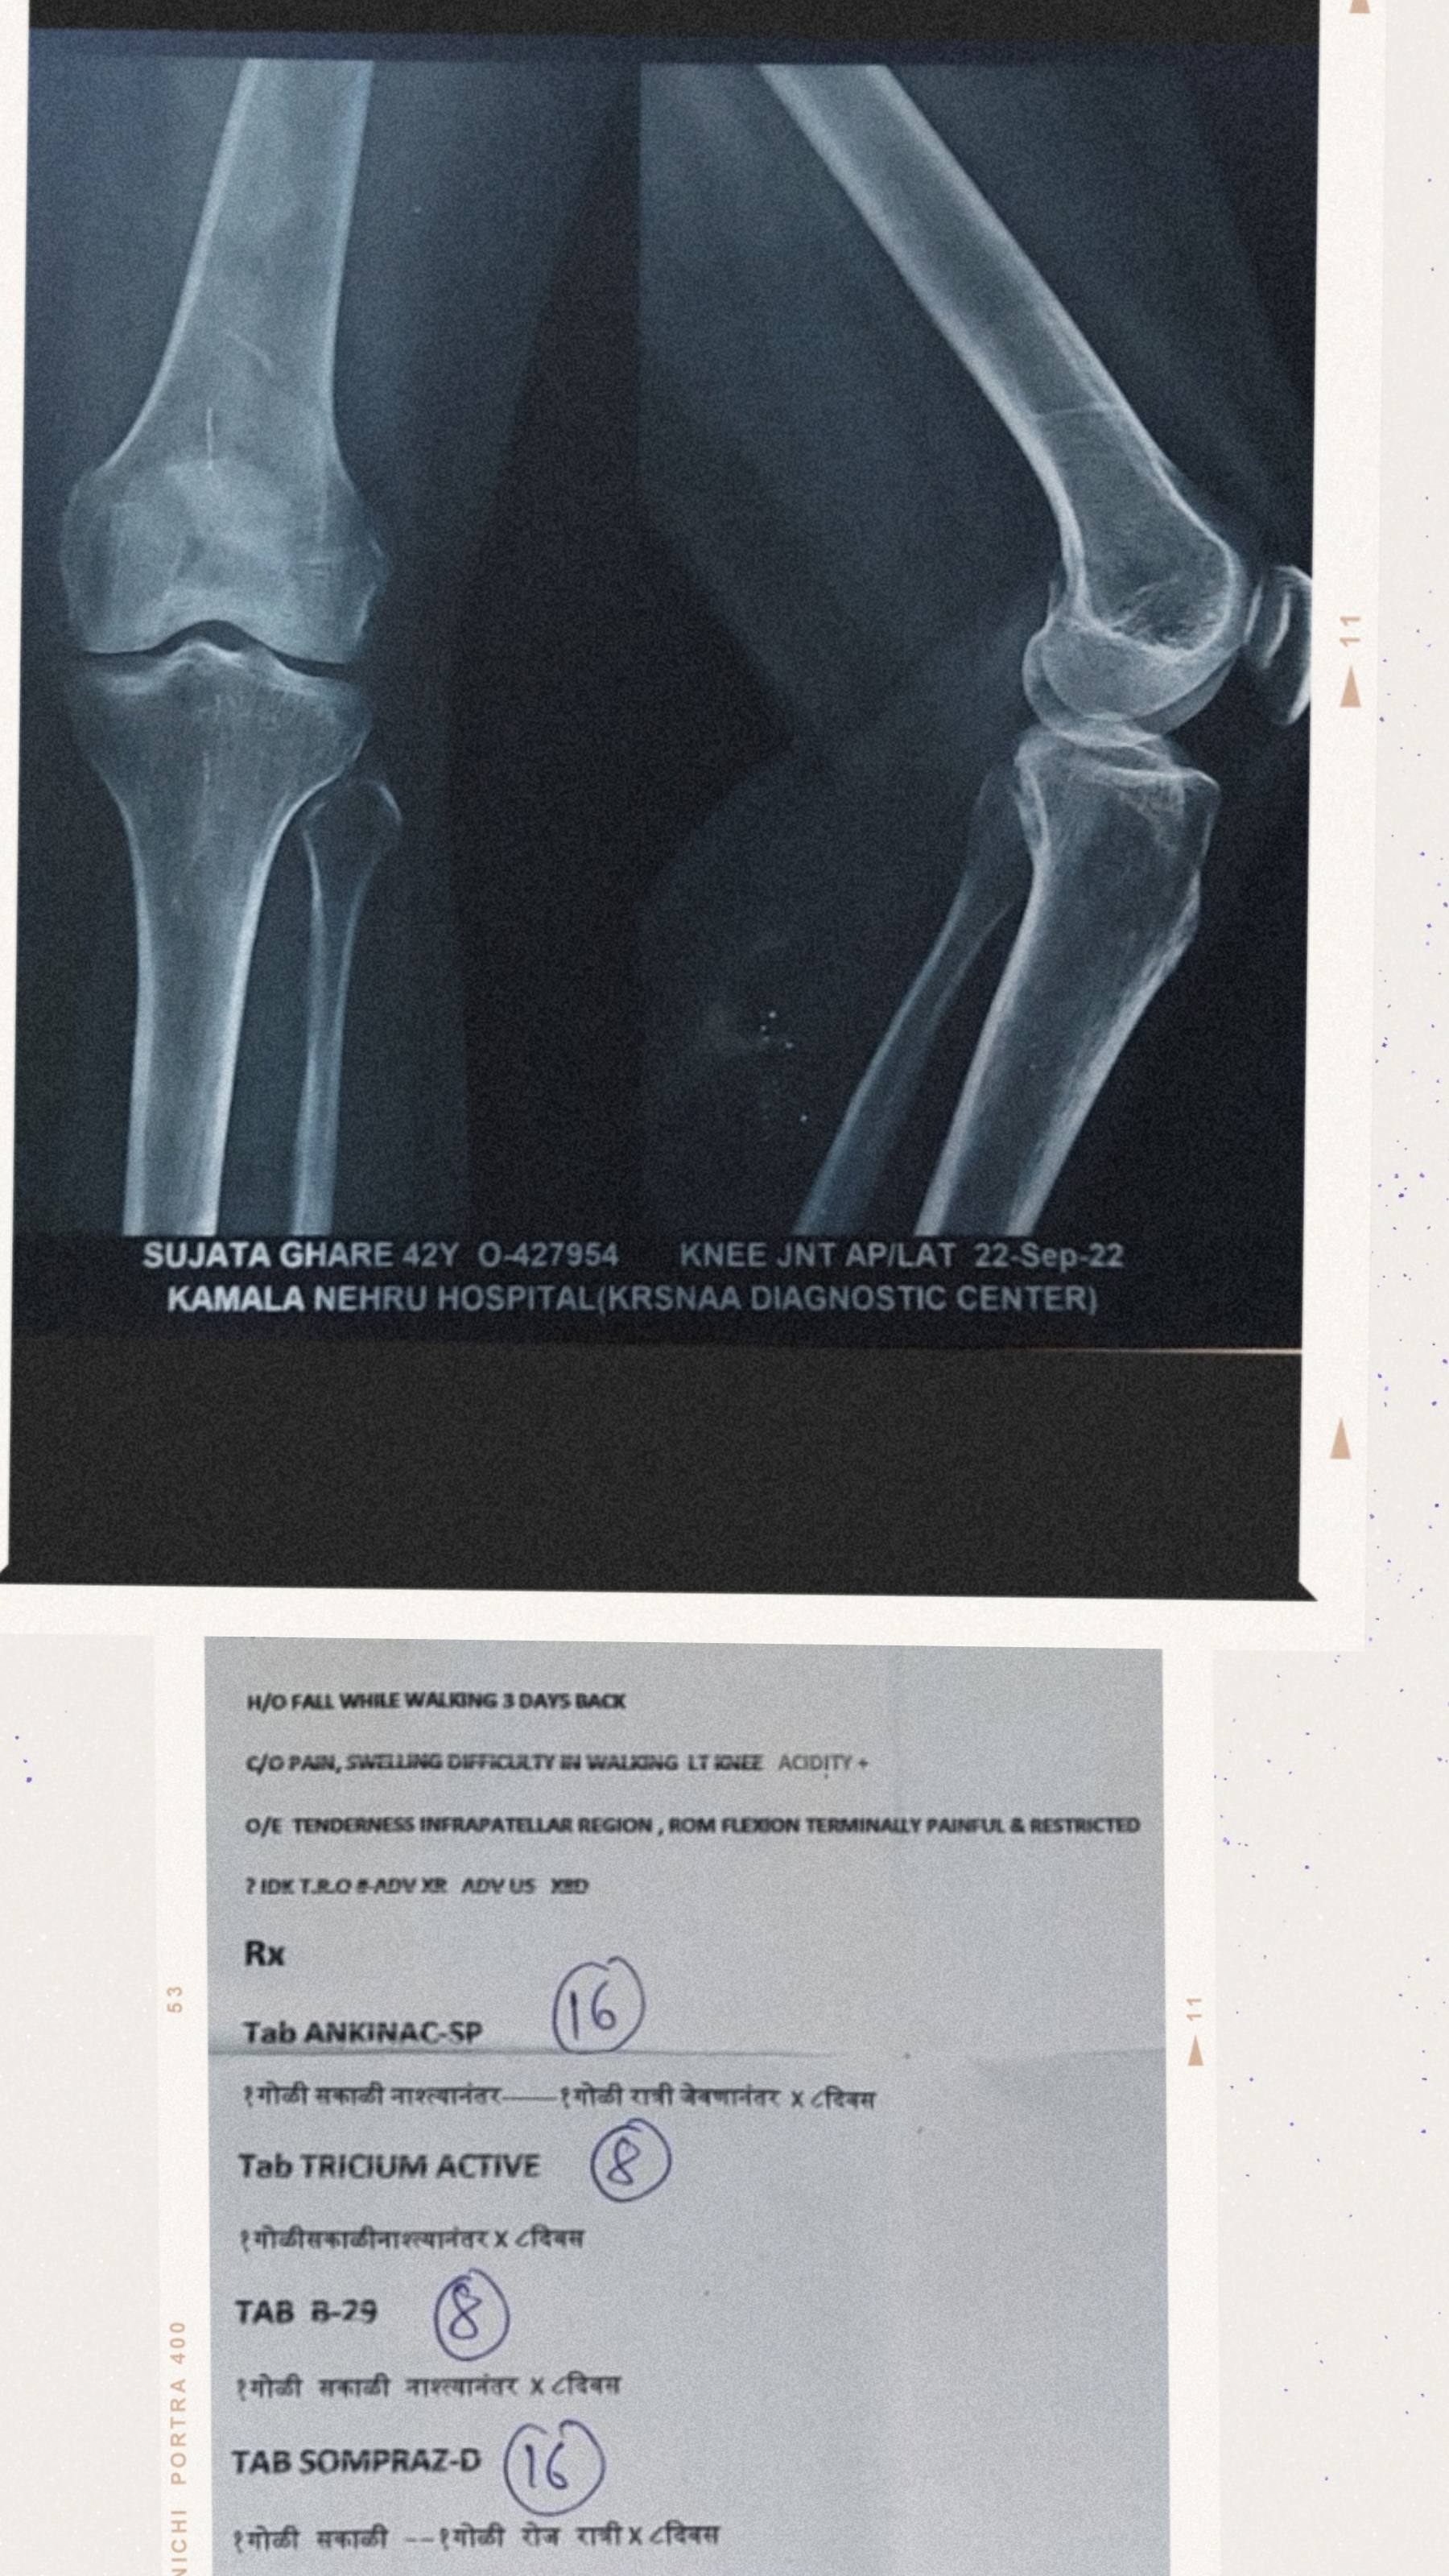

I m suffering from knee pain.

Since Last 3 months..I am having severe pain in my left knee. Xray reports are  saying that it's a hit to bone( I have attached the report kindly take a look), according to doctor and his guidelines I did followed the physiotherapy for pretty long time. Follow some regular exercises too, since there is no improvement.

While walking accidentally my left leg got folded backwards and caused pain in my knee..for few days I wasn't able to stand and walk..after 3 months now I can atleast walk a little bit and fold my leg at knee(roughly) still I can't climb stairs, and inflammation occurs behind my knee which causes pain. Can't stand for long time.

Doctors are suggesting me to wait for 5/6 months coz this is how long it takes to cover, but still I need it would help if you suggest something.